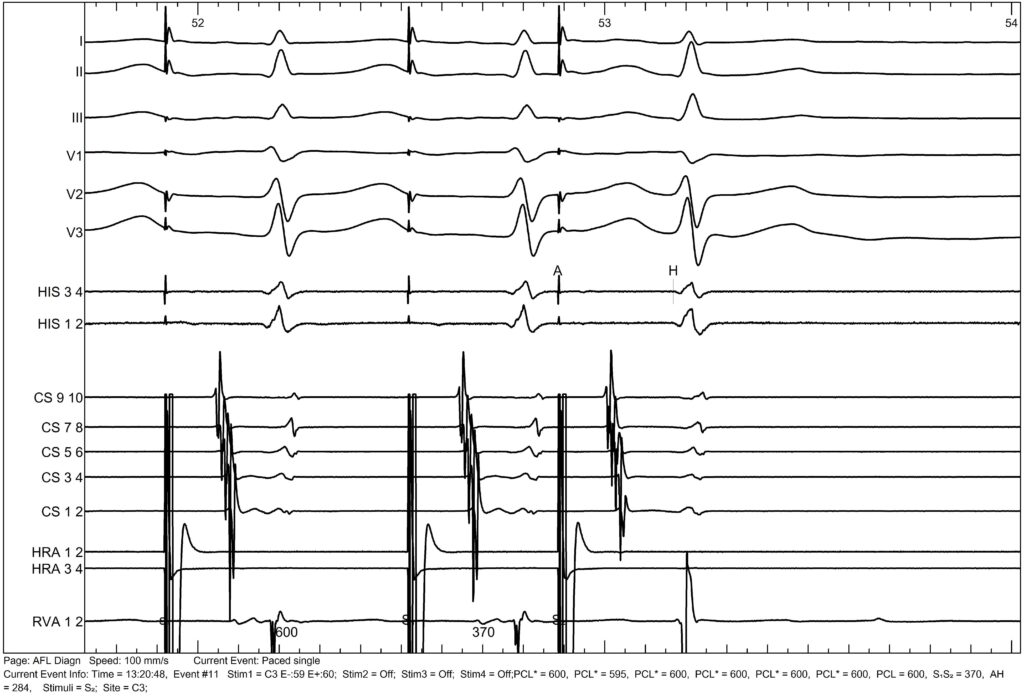

After induction of the tachycardia, we deliver a synchronous ventricular extrastimulus here, without any modulation of the tachycardia.

This is less suggestive of an AVRT.